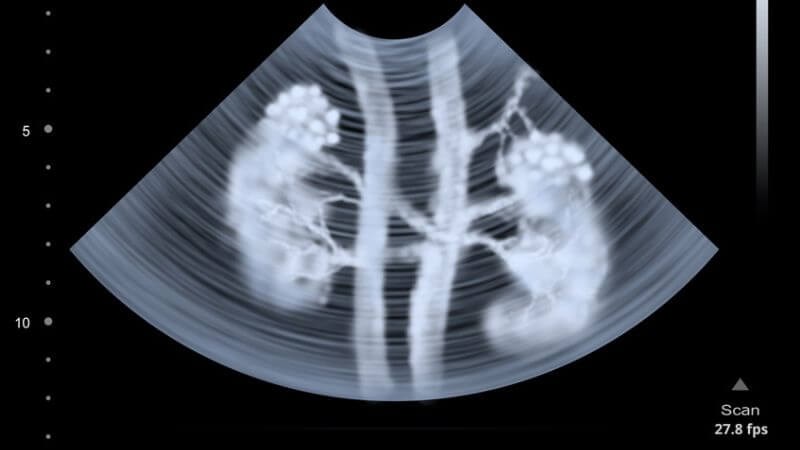

Do các triệu chứng bệnh nang thận không đặc hiệu nên thăm khám lâm sàng không thể giúp chẩn đoán bệnh lý này mà chỉ giúp hướng đến các bệnh lý về thận. Để chẩn đoán được bệnh nang thận, bác sĩ sẽ sử dụng siêu âm ổ bụng để chẩn đoán một số vấn đề như:

- Có nang thận hay không?

- Kích thước nang thận.

- Số lượng nang thận.

- Bản chất nang thận là lành tính hay ác tính.

Ngoài ra, trong trường hợp siêu âm nghi ngờ nang thận ác tính, bác sĩ có thể sẽ chỉ định thêm CT - scan để đánh giá thêm.

Siêu âm là phương pháp tiện lợi để chẩn đoán và theo dõi bệnh nang thận